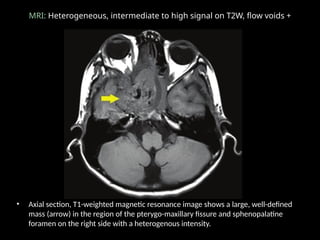

MRI: Heterogeneous, intermediate to high signal on T2W, flow voids +

• Axial section, T1-weighted magnetic resonance image shows a large, well-defined

mass (arrow) in the region of the pterygo-maxillary fissure and sphenopalatine

foramen on the right side with a heterogenous intensity.